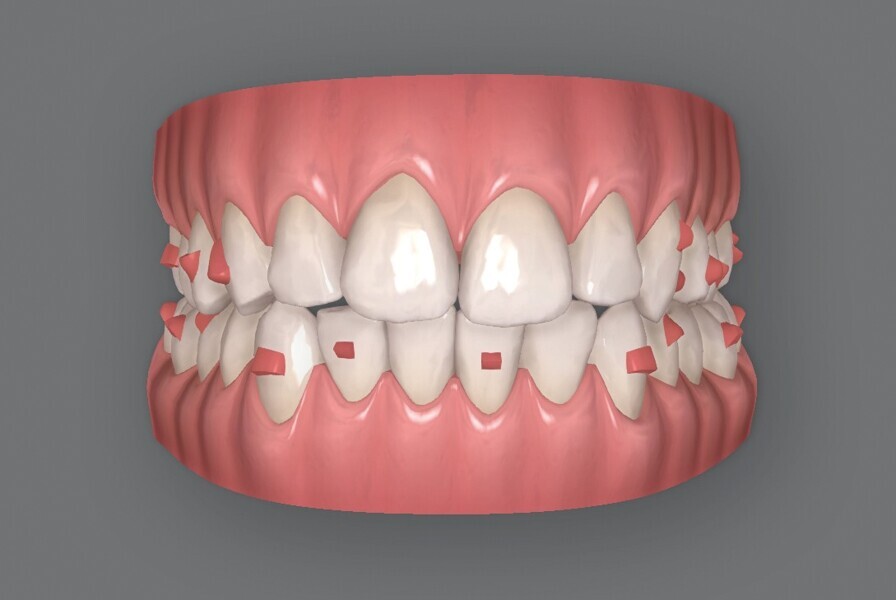

Le motif principal de consultation de la patiente, une jeune femme de 27 ans, est un encombrement dentaire accompagné d’une occlusion mal équilibrée. Danseuse de profession, elle se tracasse énormément au sujet de son apparence lors de ses apparitions publiques si elle entreprend un traitement. L’examen clinique révèle une relation d’Angle de classe I du côté droit et une relation molaire canine de classe II du côté gauche (Fig. 1).

De ce côté, les molaires, les prémolaires et la canine sont en occlusion croisée. L’examen ne montre aucun déplacement latéral fonctionnel de la mandibule. La ligne médiane maxillaire est en harmonie avec la symétrie faciale, mais la ligne médiane mandibulaire est déviée vers la gauche, en raison d’un décalage des dents de 4 mm. On observe un encombrement important des dents inférieures, évalué à 11 mm, et un encombrement modéré de 10 mm au niveau de l’arcade maxillaire. Les racines des dents 31, 33 et 43 semblent proches du rebord vestibulaire de l’os cortical, et les deux arcades présentent un rétrécissement dans la région des prémolaires et molaires.

Fig. 1b : Photographie intraorale initiale.

Fig. 1c : Photographie intraorale initiale.

Fig. 1d : Photographie intraorale initiale.

Fig. 1e : Photographie intraorale initiale.